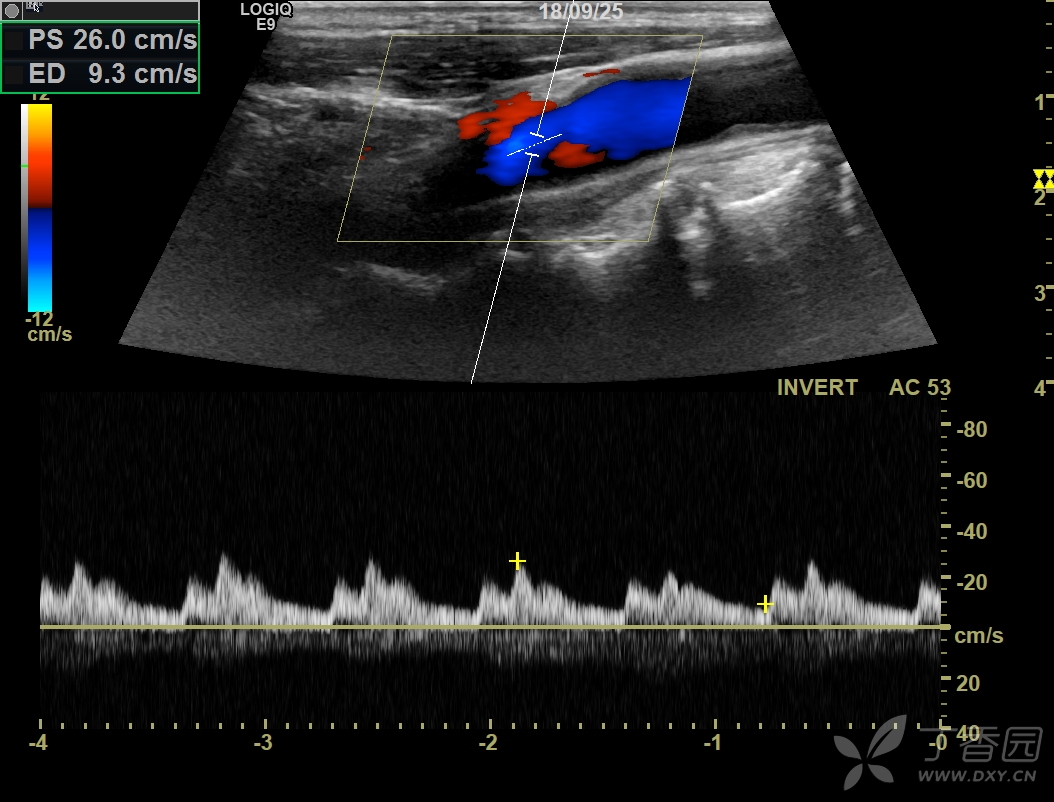

再看左侧颈总动脉与椎动脉右侧颈总动脉与椎动脉血流频谱方向完全倒置

图片尺寸960x720